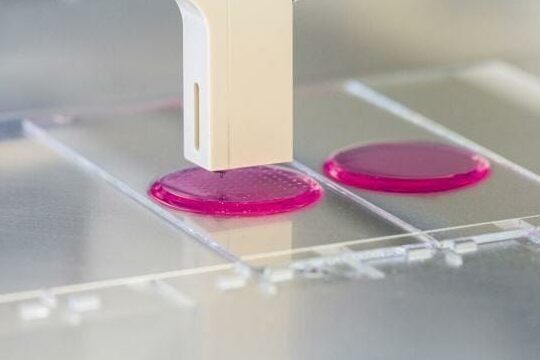

La bio-tinta ha revolucionado el campo de la medicina regenerativa, ofreciendo oportunidades sin precedentes para la impresión...